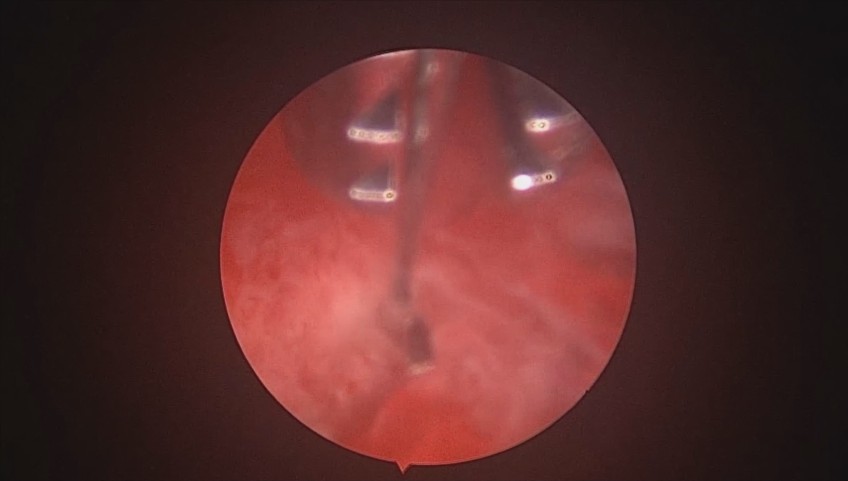

患者37岁,G3P1,剖宫产1次。子宫腺肌症合并子宫肌瘤6年,月经量增多1年。B超子宫前位,6.6cm*5.5cm*5.8cm大小,子宫后壁肌瘤直径6cm。2024年12月宫腔镜探查,宫深9cm,放置曼月乐并固定。用曼月乐尾丝在环横臂中间套扎形成线圈,异物钳夹持线圈挂到不锈钢挂钩里,将环固定于宫底,患者及家属拒绝内膜送病检。术后多次复查B超,曼月乐位置正常,最后一次环顶端距宫底1.2cm。